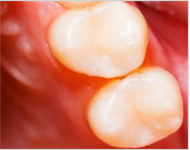

材料填充,即时雕刻外形,除去超过咬合面过高的部分,以防刺激牙龈引起炎症。